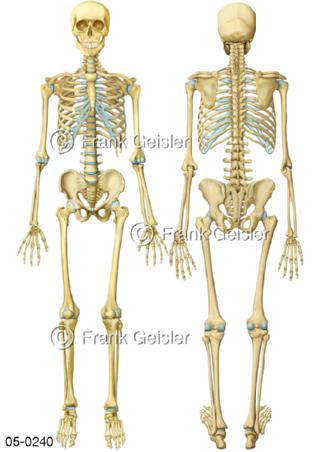

Bildergalerie Skelettsystem

Bilder zum Skelettsystem zeigen die Stützstruktur des menschlichen Körpers, die Knochen, eine besonders harte Form des Bindegewebes und Stützgewebes, welche das menschliche Skelett bildet, die Knochen des Stammes, der Extremitäten sowie der Gelenke